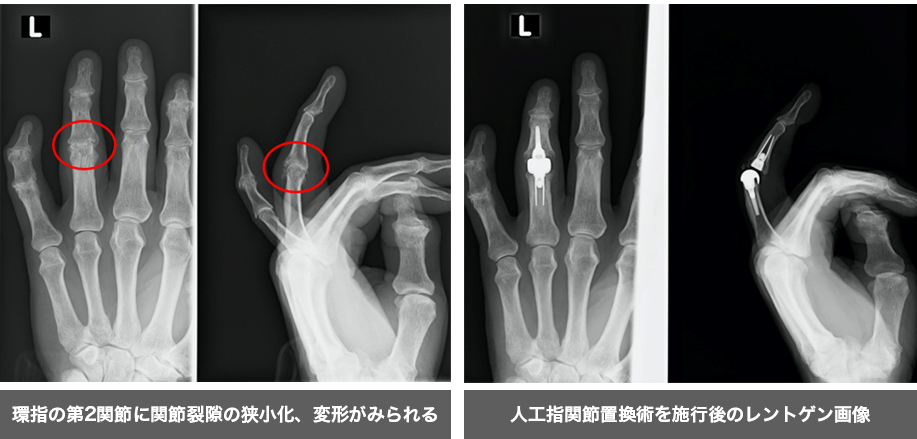

指の第2関節に変形、腫脹、疼痛と可動域制限をきたす疾患です。

特に閉経前後や更年期以降の女性に多くみられます。

保存療法(テーピング・注射・装具療法)を行い、痛みの改善が見られない場合には人工関節等の手術療法を行なうこともあります。